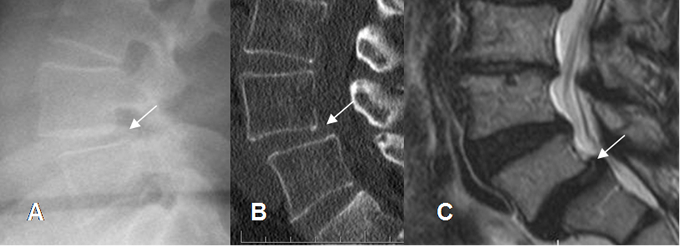

Fig 77. Anterolistesis G I.

A: Rx lateral, B: TAC reconstrucción sagital y C: RM sagital en T2. Anterolistesis GI, con desplazamiento del cuerpo superior, menor del 25%.